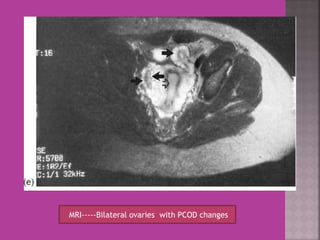

MRI-----Bilateral ovaries with PCOD changes